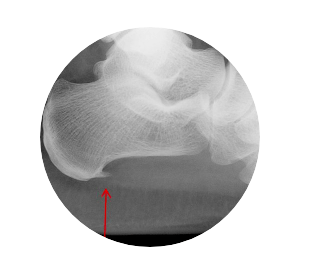

Heel Pain

Heel pain is extremely common, most heel pain is caused by plantar fasciitis. However, it can also be caused by a stress fracture, tendonitis or arthritis.

Plantar fasciitis is an inflammation of the band of tissue that extends from the heel to the toes.

The most common cause of plantar fasciitis is over excursion. Plantar Fasciitis can also become prominent due to an underlying biomechanical issue such as a high arch. Unsupportive footwear can also be a contributing factor.